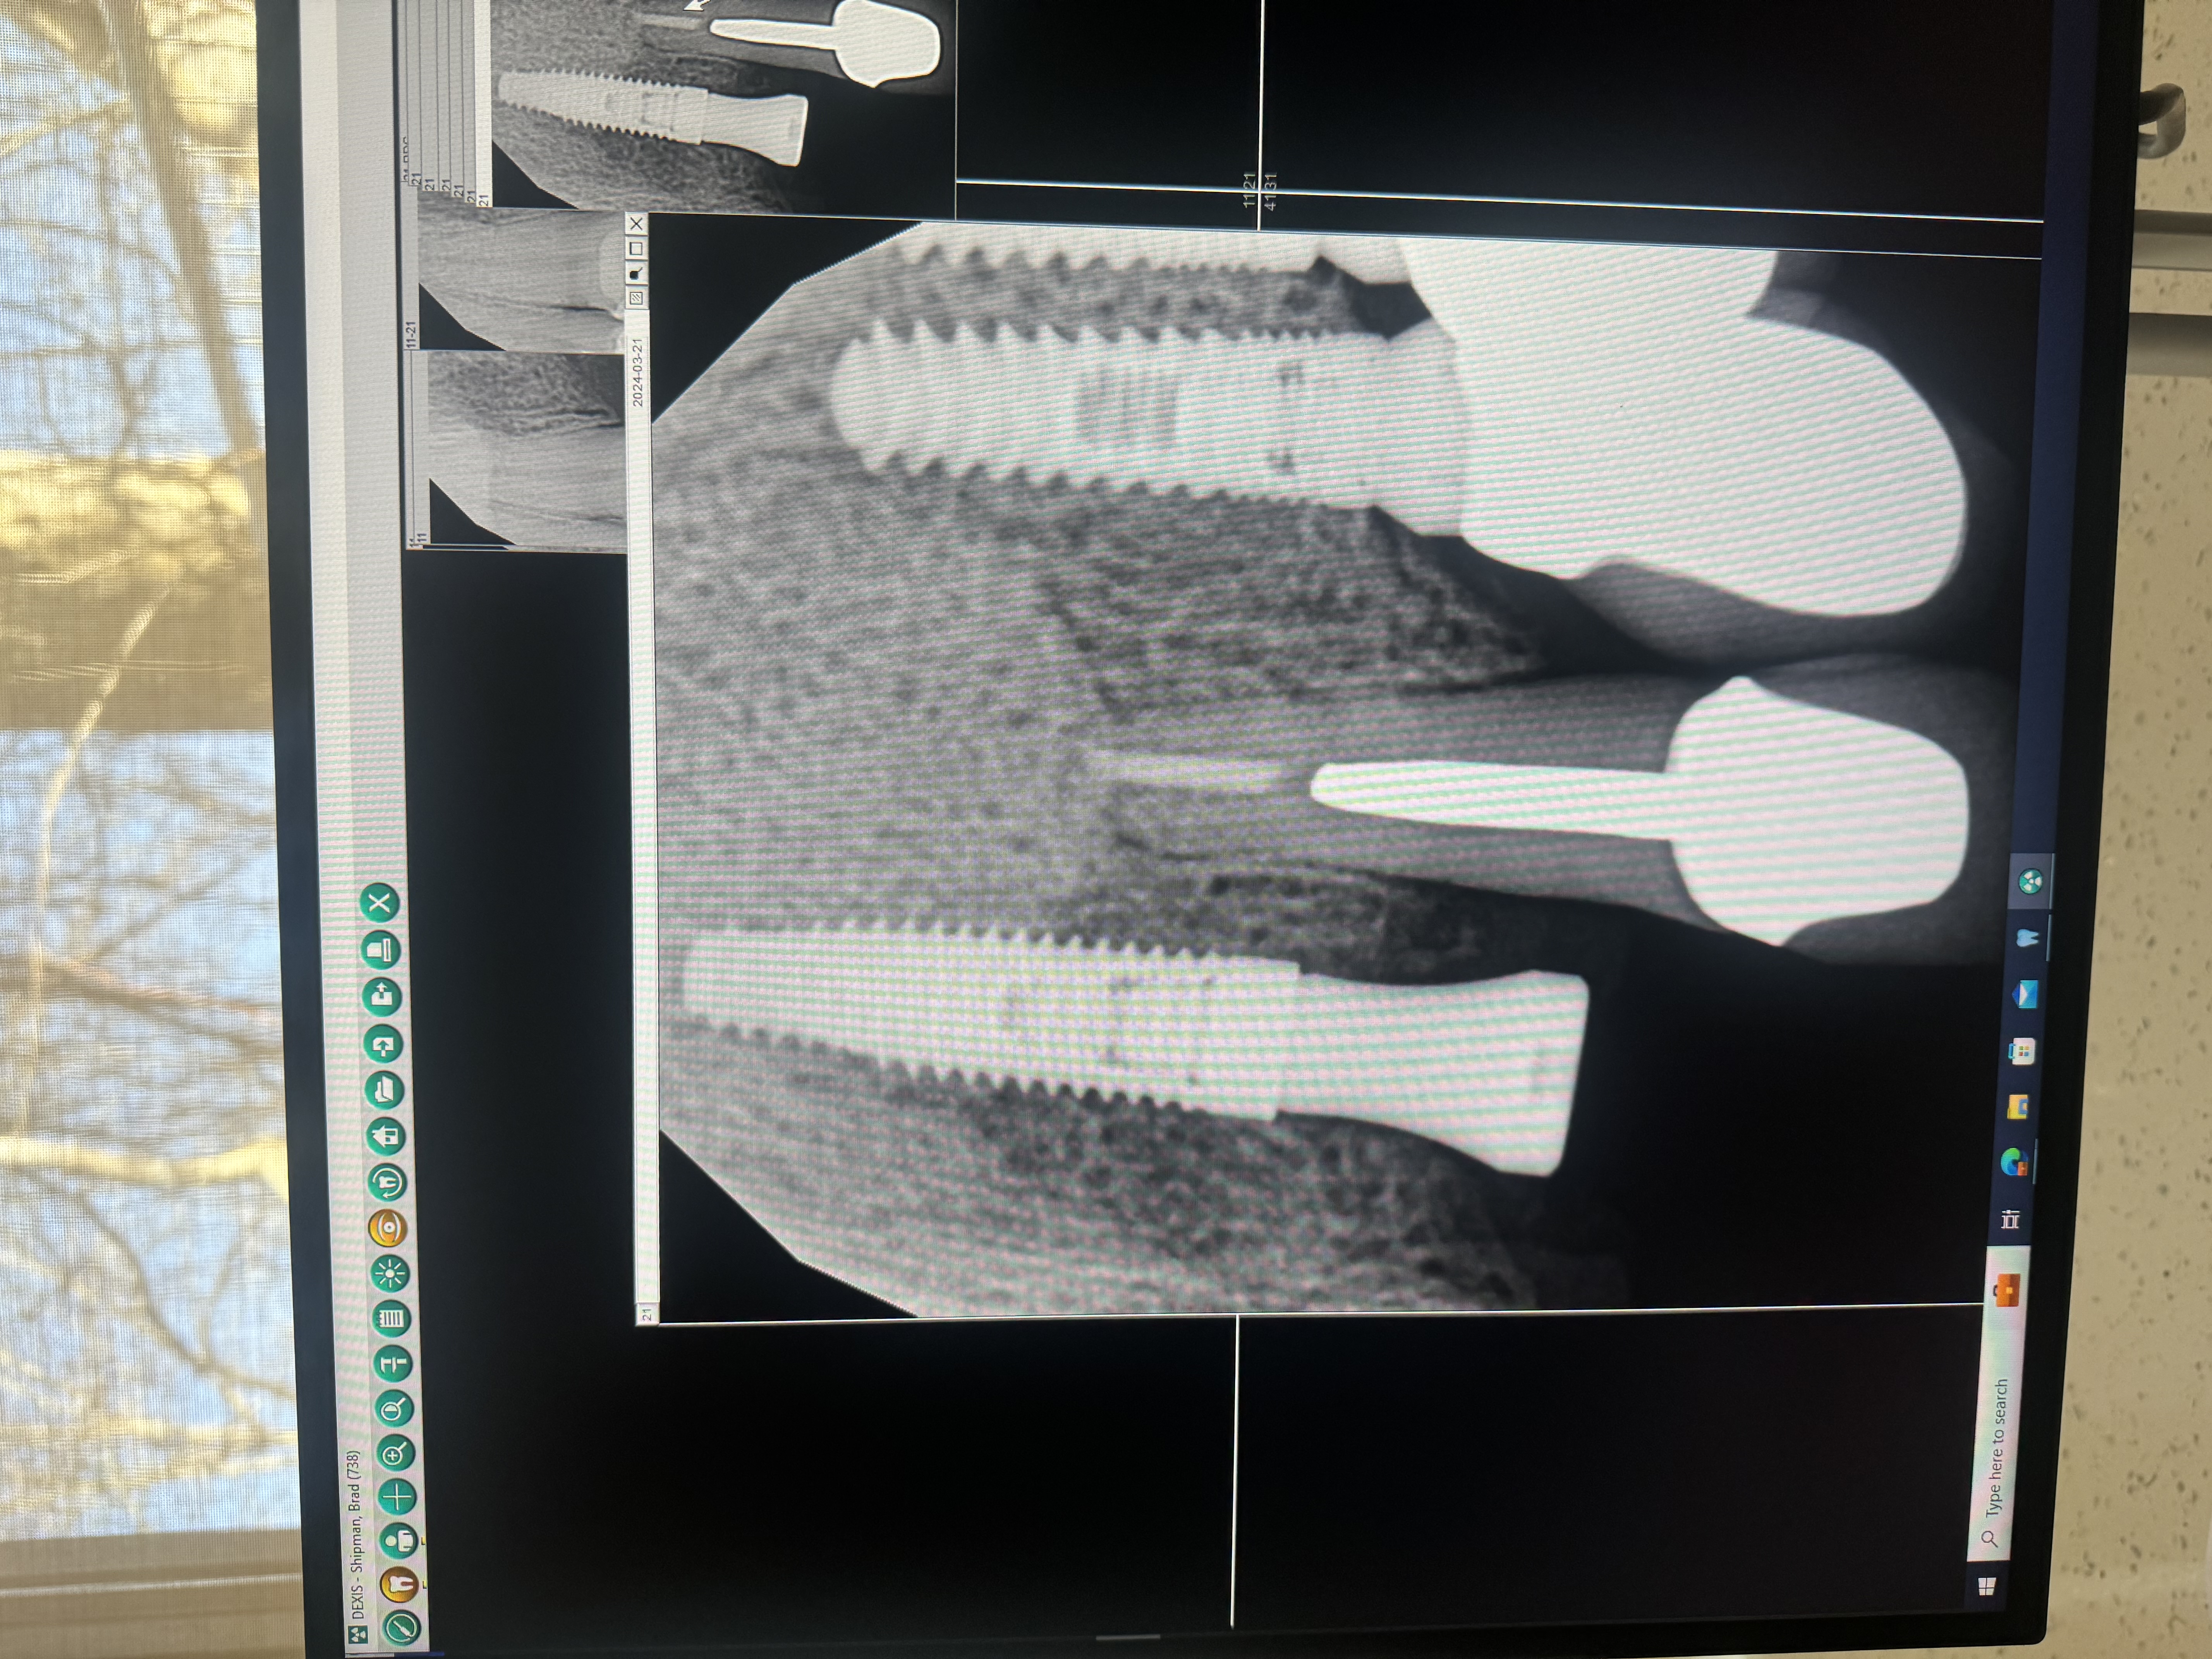

Dental implants are titanium posts that act as artificial tooth roots, surgically placed into your jawbone to support replacement teeth. Through a natural process called osseointegration, bone cells grow around and fuse with the titanium — making implants the only tooth replacement that prevents bone loss and maintains your facial structure.

Once healed, implants look, feel, and function exactly like natural teeth. You can eat anything you want, brush and floss normally, and forget they're even there. Implants have been used successfully for over 50 years with a 95–98% long-term success rate.